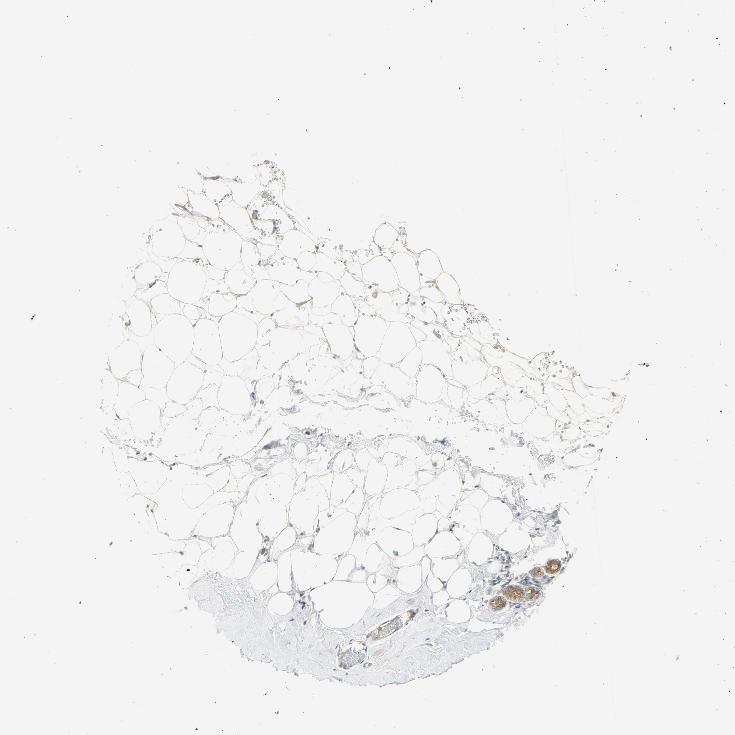

BREAST - Antibody stainingi

Antibody staining in the annotated cell types in the current human tissue is reported as not detected, low, medium, or high, based on conventional immunohistochemistry profiling in selected tissues. This score is based on the combination of the staining intensity and fraction of stained cells.

Each image is clickable and will lead to virtual microscopy that enables deeper exploration of all samples and also displays staining intensity scores, fraction scores and subcellular localization as well as patient and tissue information for each sample.

Antibody HPA004827

Adipocytes Not detected

Glandular cells Medium

Myoepithelial cells Low